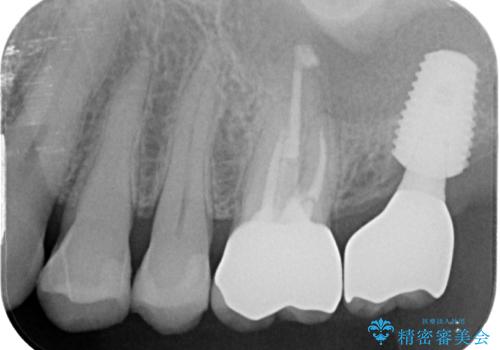

奥歯の欠損部はインプラントによる補綴治療を、手前の破損したクラウンは作り替えをご希望でした。

しかしながら、レントゲンやCT画像から、手前の破損したクラウンの根尖部に大きな病変が認められ、インプラント埋入部にまで病変が及んでいることから、まずは手前の根管治療を行い、病変の正体を確認した後にインプラント埋入を行うこととしました。

口があまり開かず、インプラントの埋入角度がやや斜めとなりましたが、機能的には全く問題なく治療を終えることができました。